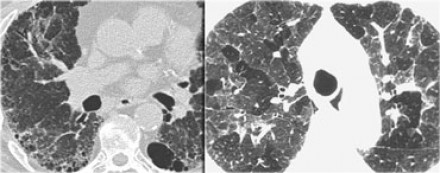

chronic hypersensitivity pneumonitis

Mosaic pattern with areas of ground-glass atenuation and areas of low attenuation.

Fibrosis and parenchymal distortion in a mid zone distribution.

left vs right?

Left UIP w honeycombing

Right Chronic HP